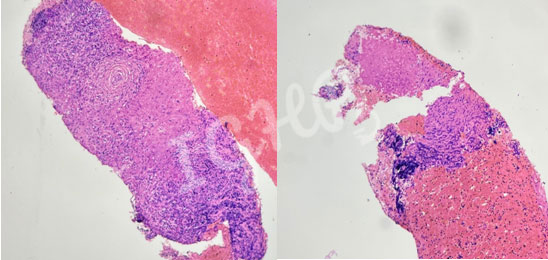

Microscopic Images-

HL is rarely associated with necrotising granuloma seenin around 1.8% cases.The Hodgkins cells are usually negative on CD45 IHC with rosetting by CD3 cells and perinuclear dot positivity on CD30 IHC and variably for CD15. The possible pathogenesis includes T cell mediated immune response against the tumor cells, tumor antigen stimulation causing fibrosis followed by granuloma formation.